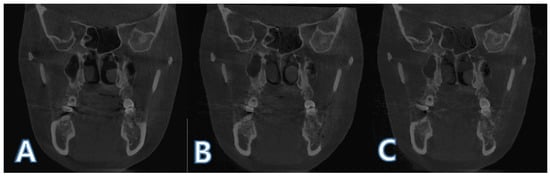

2.2. Boundary Selection of Region of Interest and Mandible Segmentation

2.3. Intensity-Based Registsration Using Segmented Mandible

2.5. ROI Image Acquisition and Boundary Separation